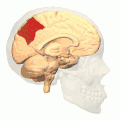

![]() Medial surface of left cerebral hemisphere. (Precuneus visible at top left.) (Anterior to the right.) | |

Precuneus of left cerebral hemisphere (shown in red). -

Medial surface of left cerebral hemisphere. (Precuneus visible at top left.) - Medial surface of left cerebral hemisphere. (Precuneus colored in red.)